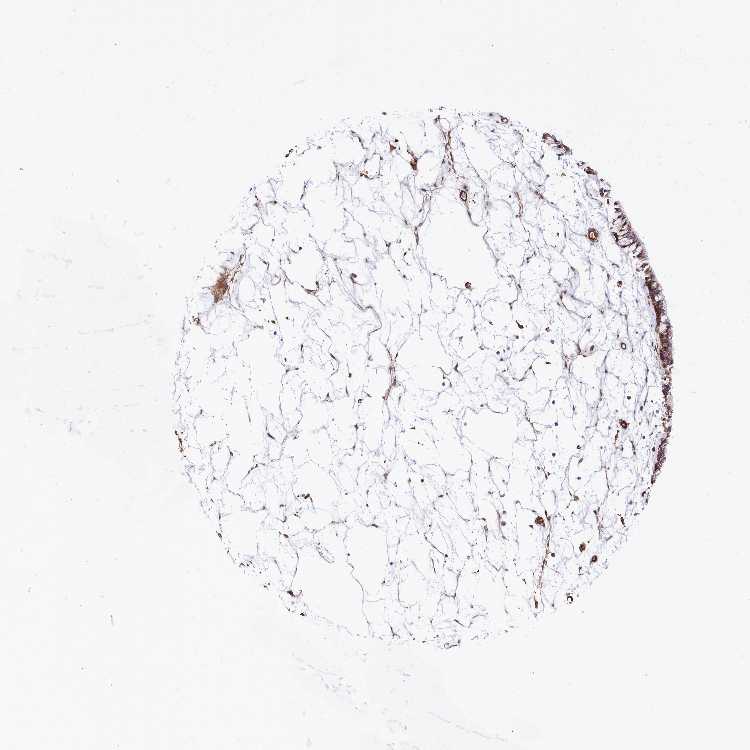

TISSUE PRIMARY DATA NASOPHARYNX Show tissue menu

NASOPHARYNX - Antibody stainingi

Antibody staining in the annotated cell types in the current human tissue is reported as not detected, low, medium, or high, based on conventional immunohistochemistry profiling in selected tissues. This score is based on the combination of the staining intensity and fraction of stained cells.

Each image is clickable and will lead to virtual microscopy that enables deeper exploration of all samples and also displays staining intensity scores, fraction scores and subcellular localization as well as patient and tissue information for each sample.

Antibody HPA037929Antibody HPA037930

Respiratory epithelial cells MediumHigh